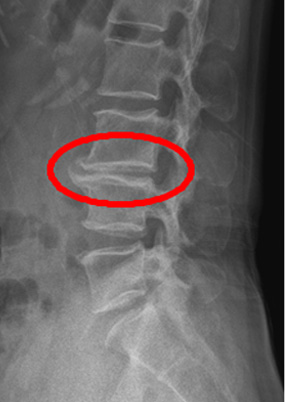

발목염좌란 내번 또는 외번 상태로 발목 근육이나 인대 섬유의 탄성 한계점을 넘어 비가역적 손상이 발생함을 말합니다. 발목은 스포츠 손상 중 신체에서 가장 많이 손상을 당하는 부분이고, 70%의 인구가 과거력을 가지고 있습니다. 손상 부위에 통증과 압통이 나타나고 부종과 멍이 생기며 체중 부하의 어려움이 나타납니다. 발목 염좌 환자들에게 있어서 가장 먼저 비골근에 약화가 오고 발목 불안정성에 영향을 끼칩니다. X-ray나 MRI로 골절이나 인대 파열 여부를 확인 후 휴식(Rest), 냉찜질(Ice), 압박(Compresion), 거상(Elevation) 시행하고 골절이나 염좌가 심하면 석고나 보조기를 이용하여 고정하거나 심한 경우 수술적 치료가 필요하며, 일반적인 염좌인 경우 체외충격파와 전기치료로 통증 조절을 합니다.